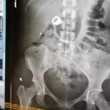

Christina Schlegel, 25 anni, e Bryan Ford, 30 anni, sono stati arrestati dopo avrebbe rubato un anello di nozze in un negozio Zales che si trova all’interno di un centro commerciale dello Utah. La polizia ha visto Ford scappare con l’anello: l’uomo è però riuscito a saltare nell’auto guidata dalla fidanzata e i due sono scappati via. La loro auto è stata fermata a breve distanza e l’anello non è stato trovato: una radiografia dello stomaco della donna ha però incastrato la ragazza, mostrando che lo aveva ingoiato.